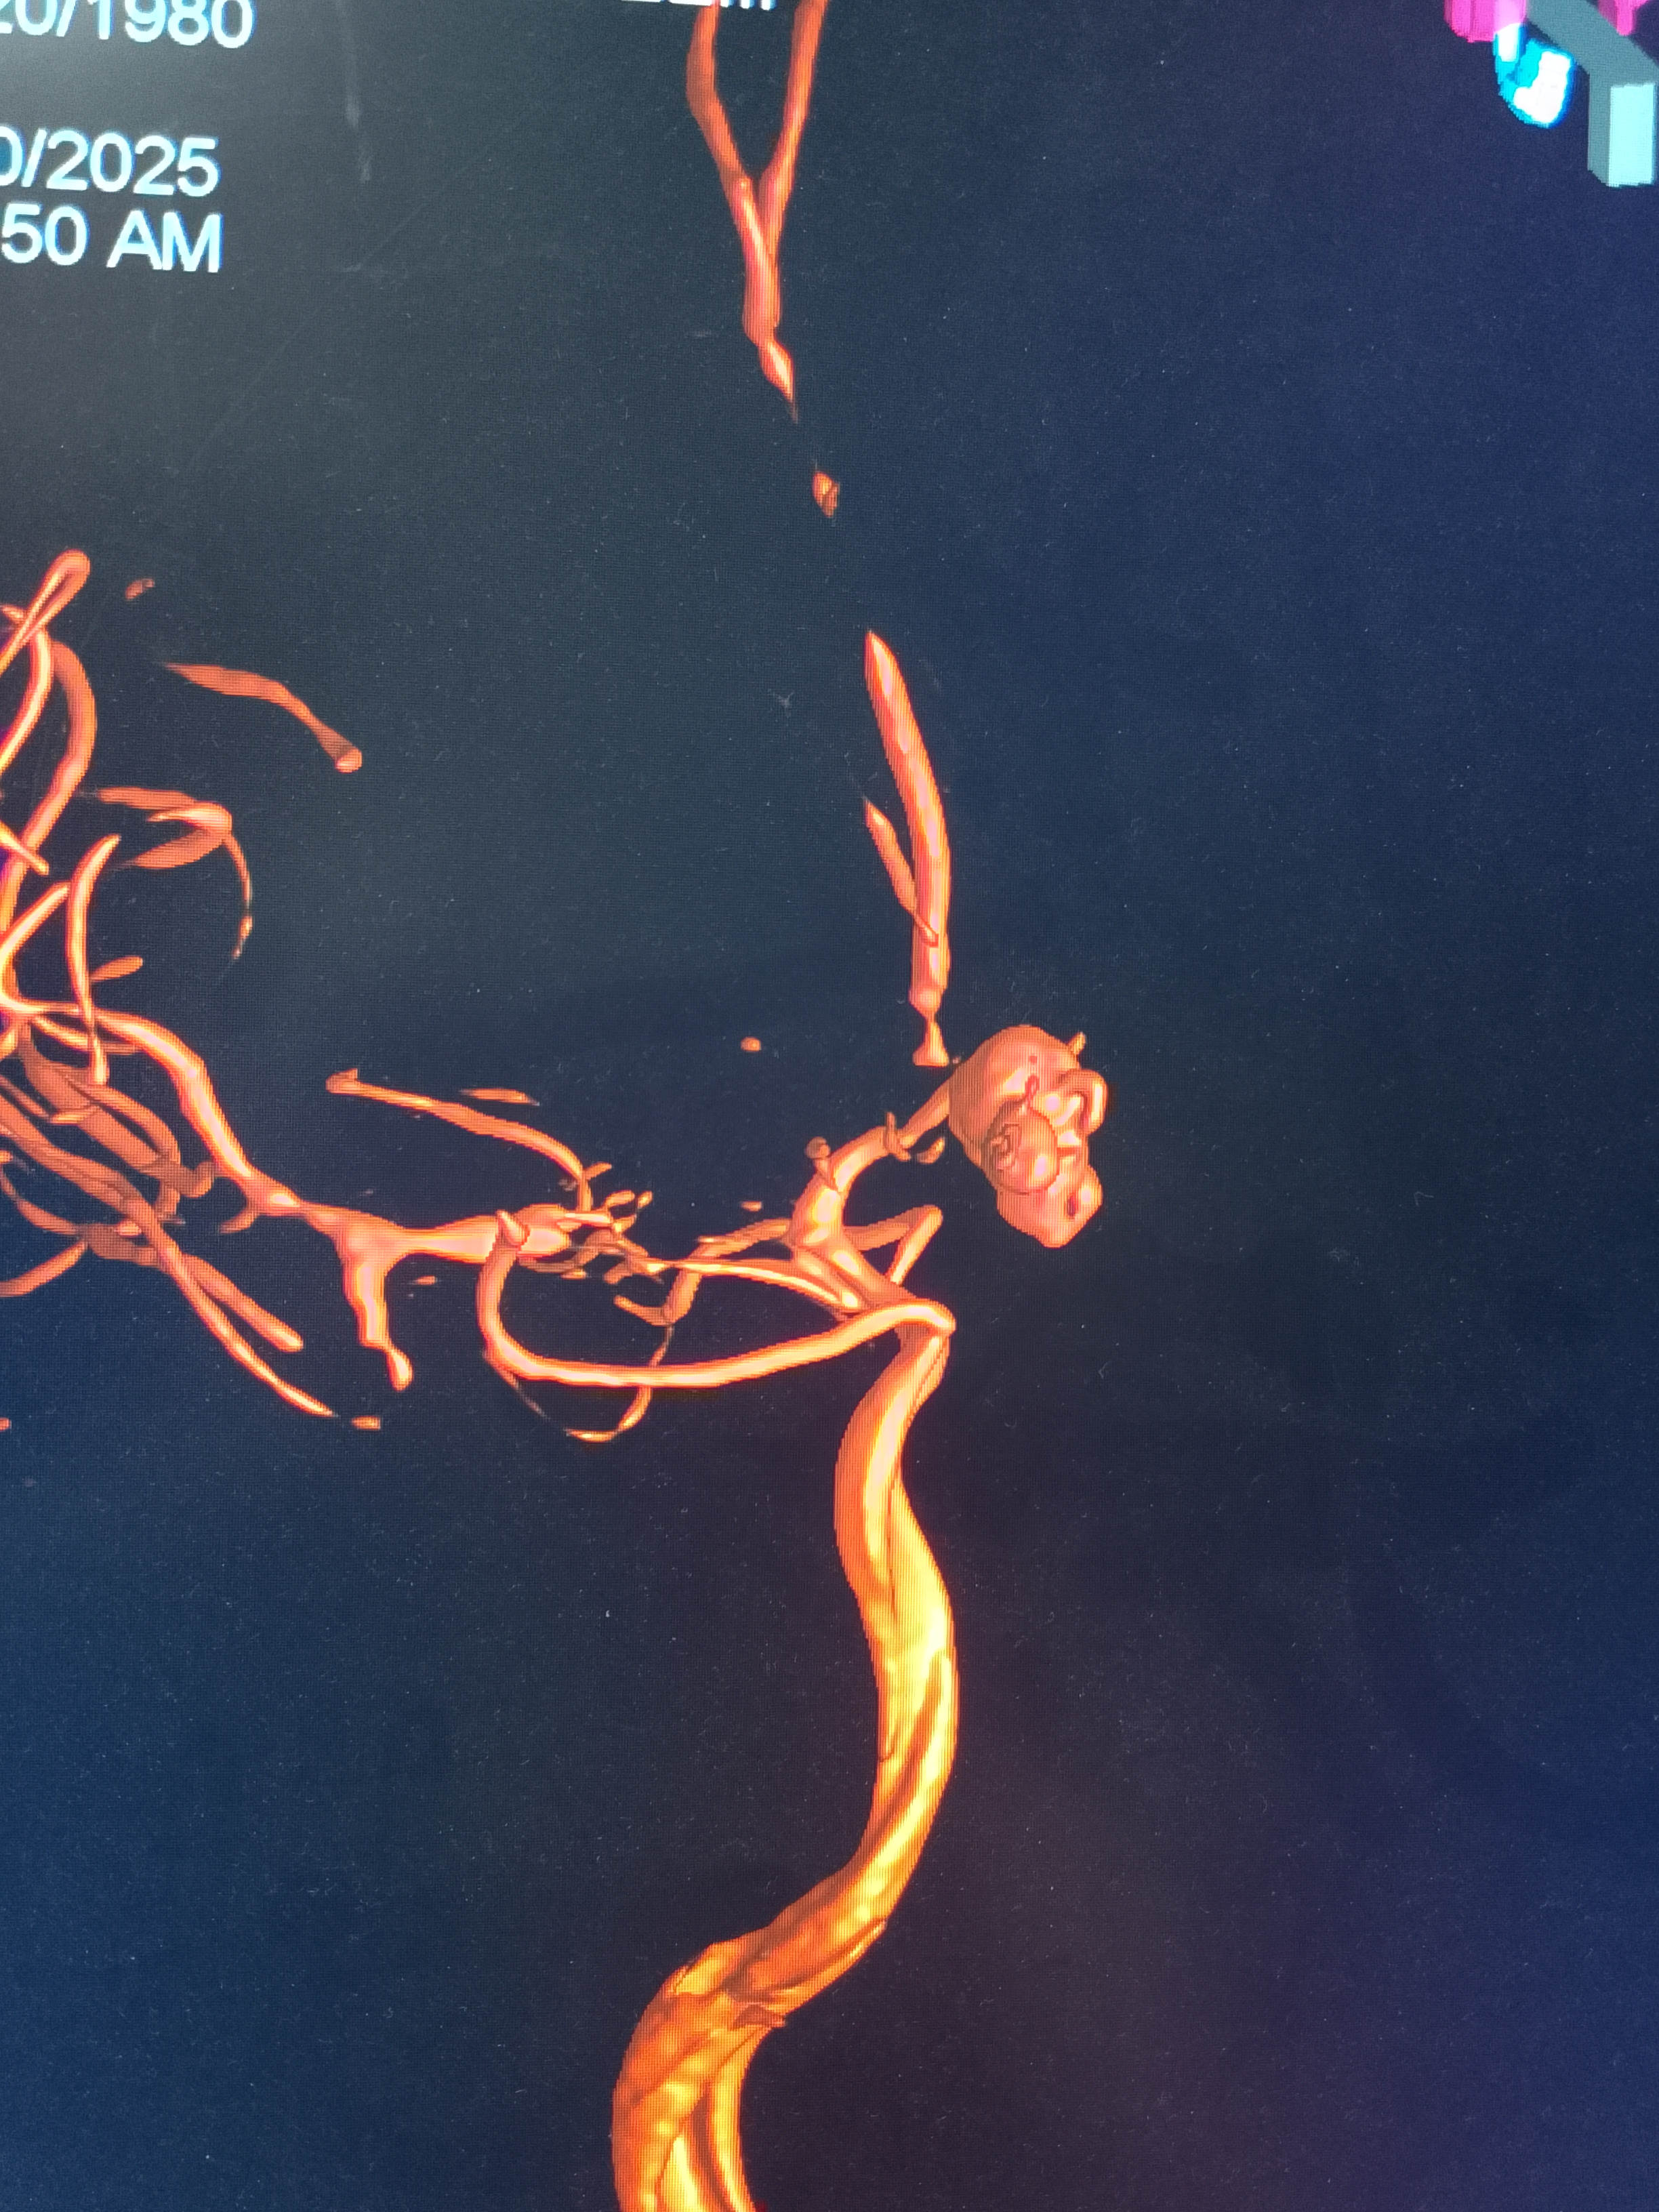

মাথা ব্যথা, ঘাড় ব্যথা, কোমর ব্যথা, পিএলআইডি সমস্যা, হেড ইনজুরি , স্পাইন ইনজুরি , স্পাইনের রড-স্ক্র ফিক্সেশন, মস্তিষ্ক - স্নায়ু - মেরুদণ্ড ব্যথা, স্পাইনাল টিউমার, ব্রেইন টিউমার, প্যারালাইসিস বা পক্ষাঘাত, স্ট্রোক, হাত - পায়ে ব্যথা, হাতে পায়ে ঝিমঝিম ভাব , শিশু নিউরোসার্জারি , ভাসকুলার নিউরোসার্জারি বিশেষজ্ঞ ও নিউরোসার্জন।